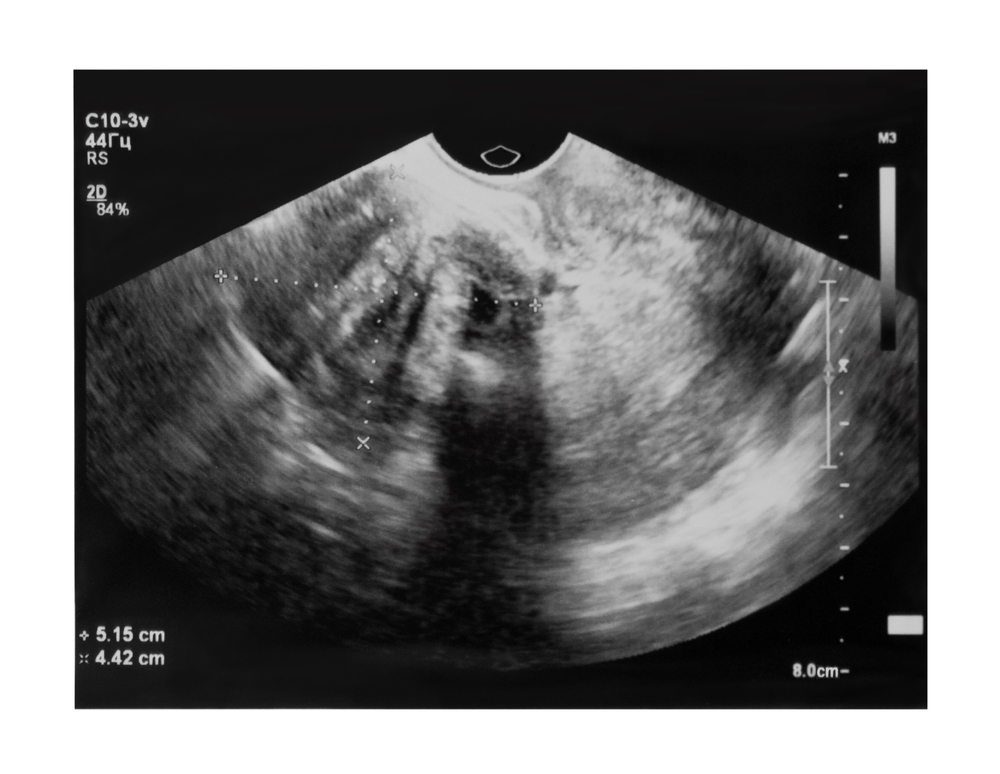

Ultrassom pélvico

A ultrassonografia pélvica é um exame indicado para o diagnóstico de mioma uterino porque possibilita a visualização do útero, do colo uterino, da vagina, das tubas uterinas e dos ovários. Ela é realizada com o auxílio de um transdutor, aparelho que emite ondas sonoras, transformando-as em imagens, em tempo real, transmitidas por um monitor. A ultrassonografia pélvica é realizada de duas formas: endovaginal (pela vagina, chamada ultrassonografia transvaginal) ou pelo abdômen (chamada ultrassonografia abdominal ou suprapúbica). Nenhuma delas requer uso de qualquer tipo de sedação ou anestesia.